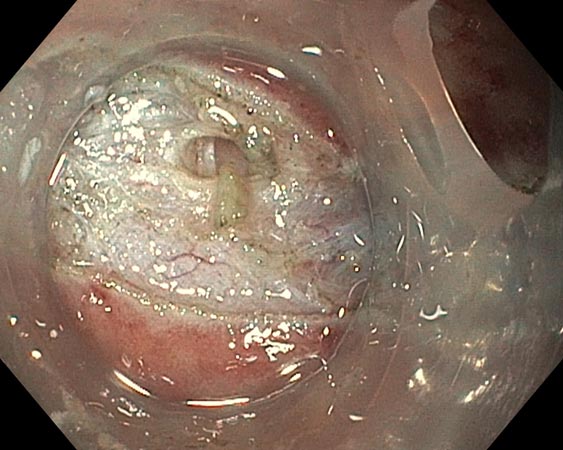

Появление налёта фибрина на 2-е сутки и увеличение его толщины на 3-и сутки после первого этапа ESD создавали определённые трудности в визуализации подслизистого слоя, но не привели к отказу от проведения второго этапа ESD (рис. 9, 10).

Рис. 9. Фибрин на 2-е сутки после эндоскопической подслизистой диссекции

Рис. 10. После отмывания фибрина